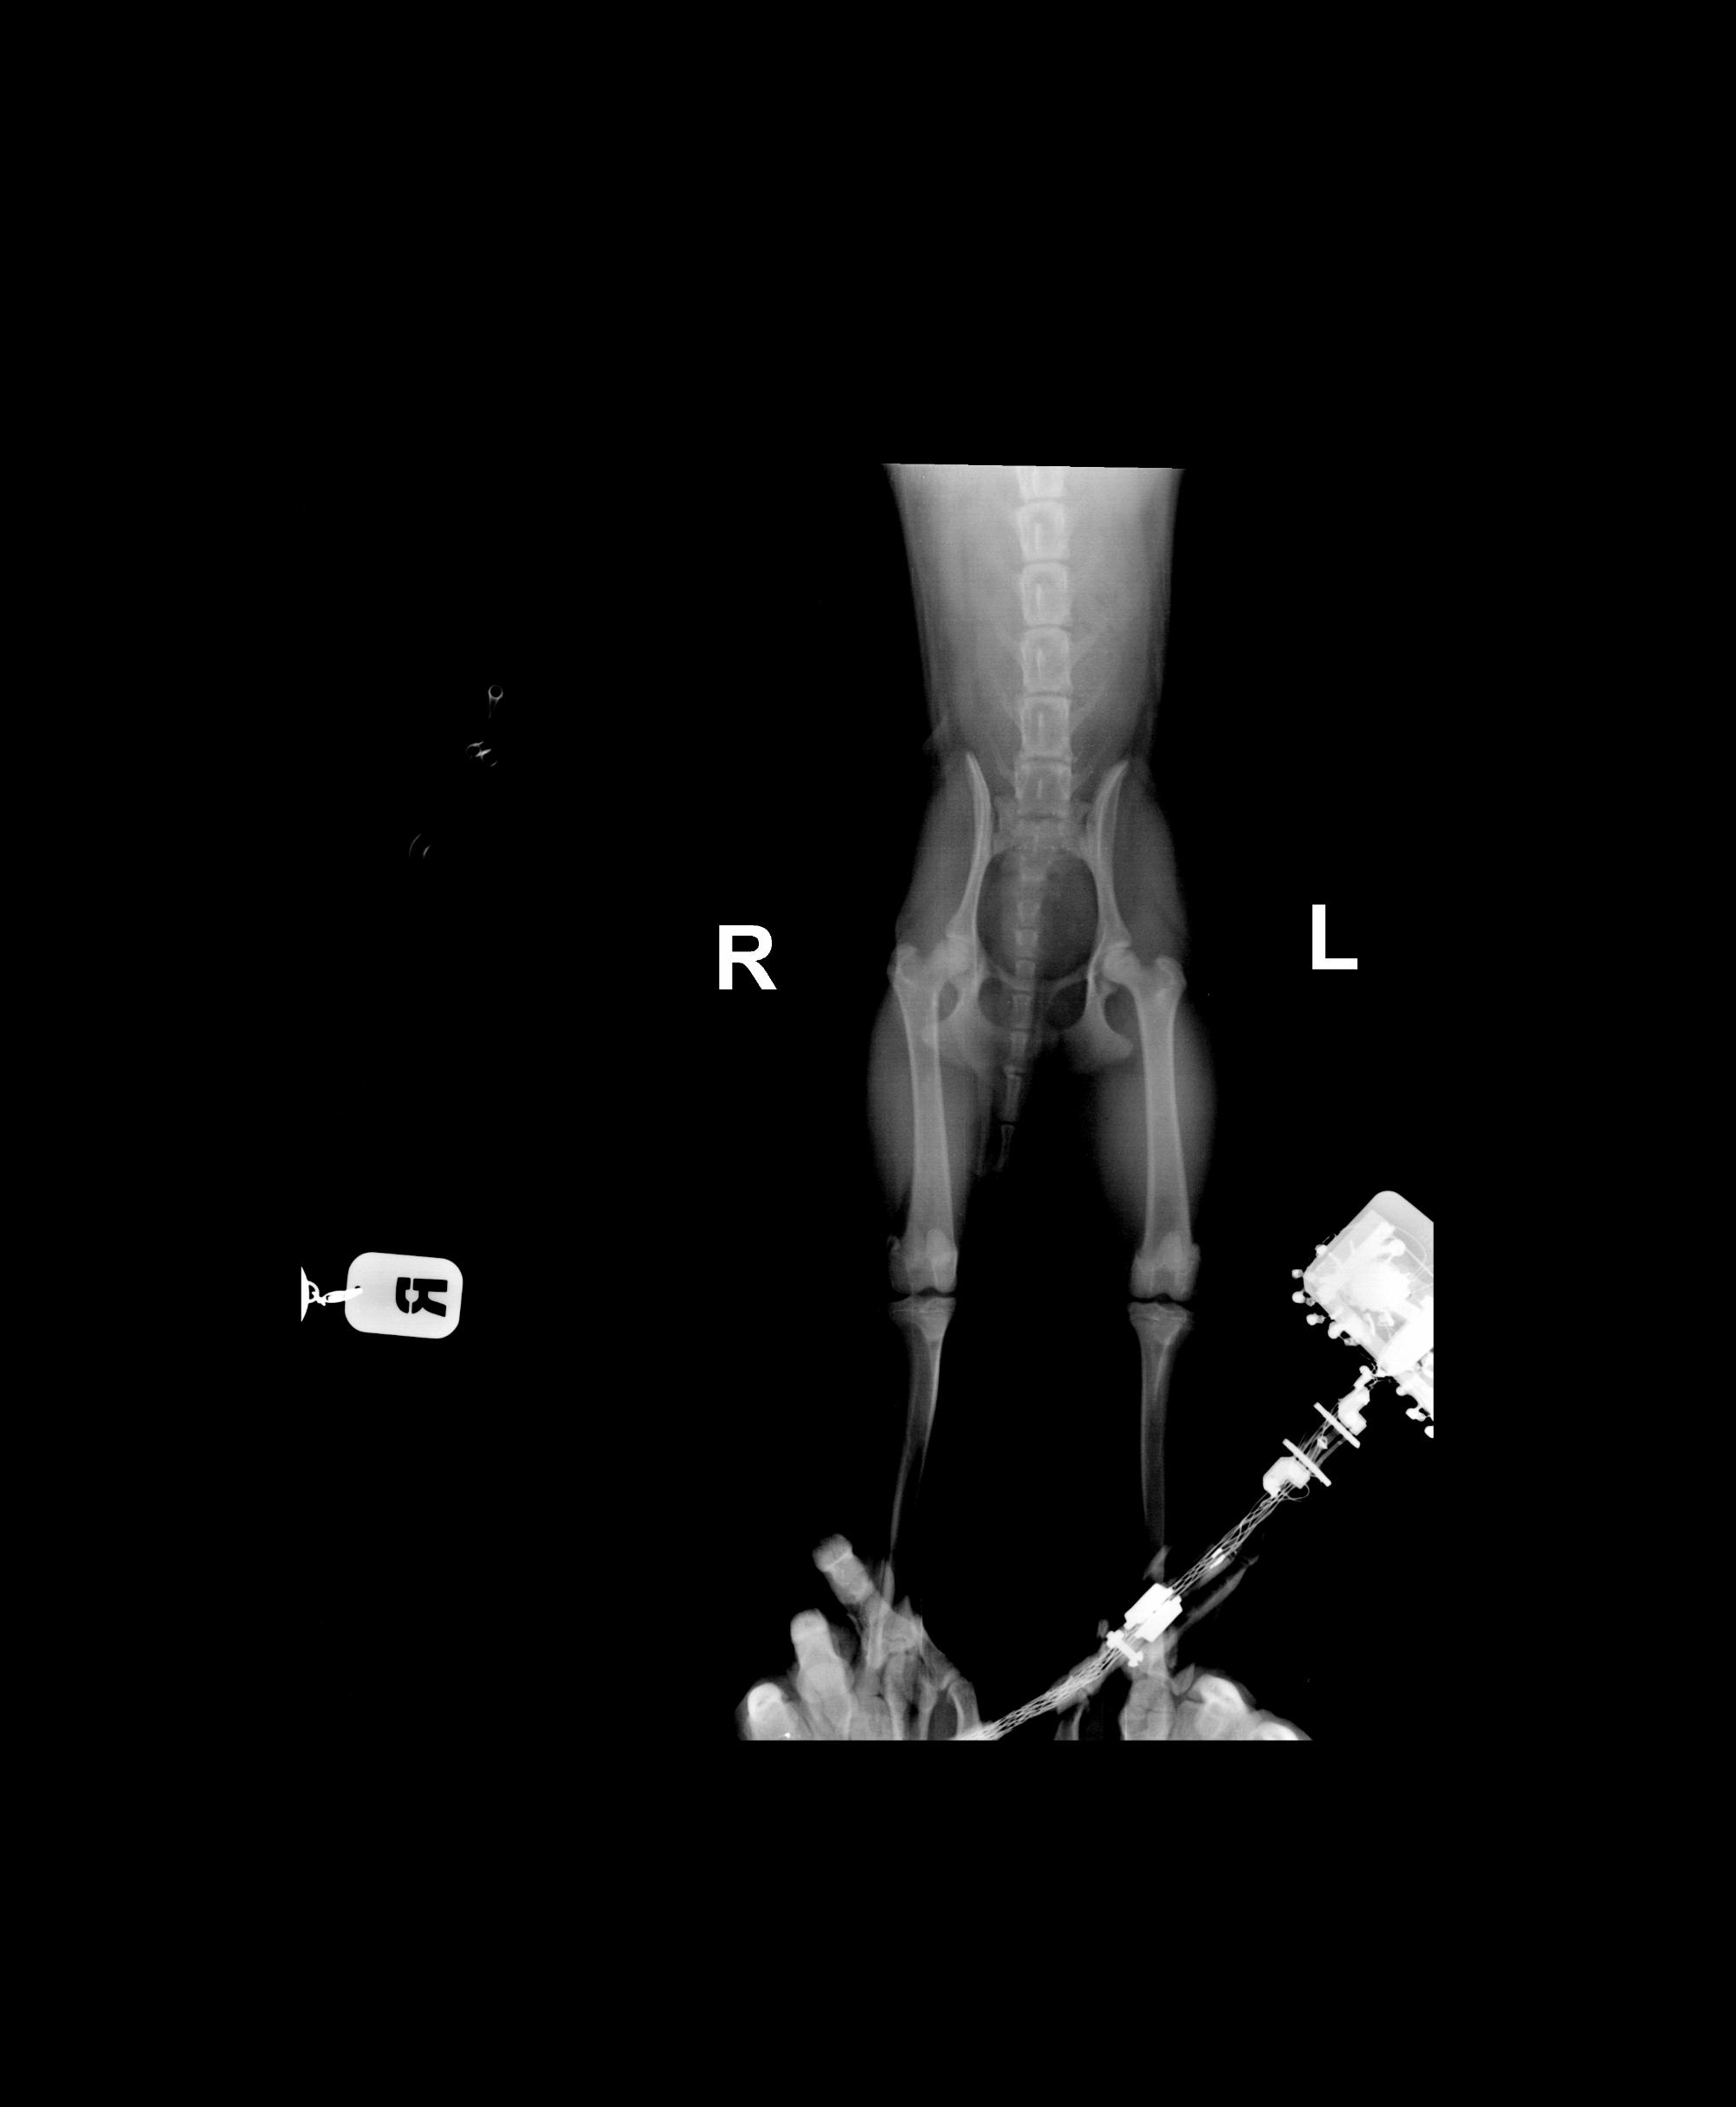

Прошу прощение за долгое молчание, работой завалило. А с другой стороны, вроде ситуация прояснилась.

Ездили в позапрошлую субботу (неделю назад) в другую клинику, (для красноярцев: в "Амикус", к Скобелеву).

Совершенно иной уровень обследования. Видимо, в "Центровете" сдохлись совсем. Даже свинцовые накладки на грудь хозяевам, когда делали снимки, не выдали. Плохие снимки не пересняли, по ним "диагностировали" трещину.

Lika-MV, к сожалению, Вы оказались абсолютно правы: это болезнь Пертеса. Причём, врач предположил это сам, после осмотра, ещё до того, как сделал снимки, несмотря на то, что заключение центровета было "трещина".

Снимков делали два, но второй снимок аж три раза: всё время Скобелева качество не удовлетворяло. Диагноз подтвердился: "асептический аваскулярный некроз головки правой бедренной кости"

причина, по словам врача, неизвестна, может удар и спровоцировал, а может и нет

хирургическое вмешательство рекомендовал по состоянию, лучше позже, чем раньше